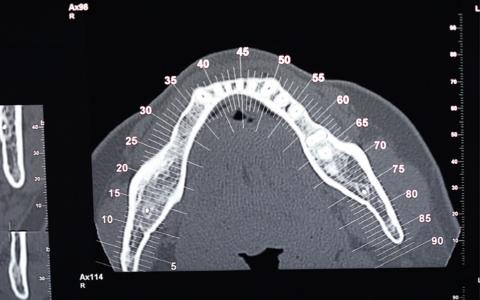

Caso Clínico nº7: Expansión ósea

Paciente de 37 años el cual llega a la consulta para recuperar los dientes 4.4- 4.5- 4.6- 4.7 se decide colocar 3 implantes ya que los espacios se han reducido gracias a la mesialización del 4.8.

Plan de tratamiento: Expansión en casos no extremos para devolver la dimensión transversal.